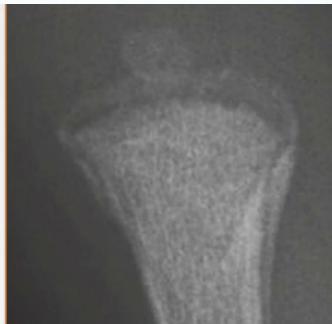

Beware! Malignant Tumors

- Can present as injury

- History of trauma is usual

Case Example:

- 12-year-old girl

- History of trauma

- Mild tenderness

- Periosteal reaction

- Initially diagnosed as injury

- 2 months later, still tender

- Final diagnosis: Ewing’s sarcoma